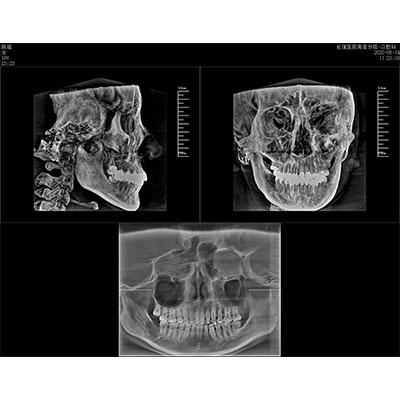

該款牙科CBCT產(chǎn)品采用動態(tài)平板探測器,獲得三維圖像的同時(shí)還具有數(shù)字化全景功能,廣泛應(yīng)用于口腔頜面外科、正畸科、正頜外科、種植科、牙體科、顳下頜關(guān)節(jié)科等術(shù)前術(shù)后。

專有三維重建算法,可提供任意位置高清斷層影像。

通過三維容積影像,提取高清口腔全景影像。

可同時(shí)觀察軸向面、冠狀面和矢狀面圖像,方便臨床診斷。